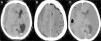

Analizamos las características epidemiológicas, los antecedentes personales, los síntomas de inicio y el tiempo de evolución, y la situación clínica de los pacientes de acuerdo con la escala de Markwalder13: grado 0: ausencia de déficits neurológicos; grado 1: paciente consciente y orientado y con sintomatología mínima como cefalea; ausencia o déficit neurológico mínimo, tal como asimetría en los reflejos; grado 2: paciente confuso y desorientado con déficit neurológico variable; grado 3: paciente estuporoso pero con respuesta a estímulos dolorosos, déficit neurológico grave; grado 4: paciente en coma sin respuesta a estímulos dolorosos, posturas de descerebración o decorticación. Así mismo, se revisaron los resultados postoperatorios y las complicaciones quirúrgicas. Todos los pacientes fueron diagnosticados empleando tomografía computarizada (TC) y agrupados en función de la estructura interna del hematoma en 4 categorías, empleando la clasificación propuesta por Nakagushi et al.14: homogéneo, laminar, separado o de densidad mixta y trabecular (fig. 1). El volumen del hematoma fue calculado de acuerdo a la ley del elipsoide modificada por Kothari (A×B×C/2) donde A=mayor largo, B=mayor ancho y C=altura)15.

Hallazgos radiológicosEl 44,5% de los hematomas (89 pacientes) estaban localizados en el hemisferio izquierdo, el 39% (78 pacientes) en el derecho y en 33 casos (16,5%) era bilateral. Con relación a la estructura interna del hematoma en los 167 casos unilaterales, 92 hematomas (55%) eran homogéneos, 55 (33%) separados o de doble densidad, 12 (7,1%) laminares y únicamente 8 (2,3%) eran trabeculares. La desviación de la línea media osciló entre 0-18mm, con una media de 6,5±4mm. En 135 casos se pudo determinar el volumen del hematoma, que osciló entre 67 y 297cc, con una media de 107,8±23,7cc (tabla 2).